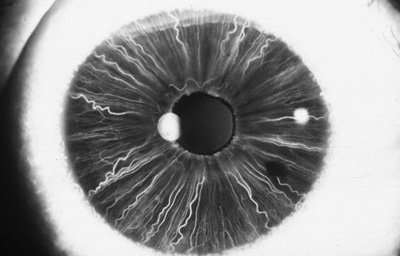

En la cara Posterior se ven pliegues radiales muy finos que se extienden desde el margen pupilar hasta el collarete ( miden ± 1.0 mm), y son conocidos como Pliegues radiales de contracción de Schwalbe. Existen ademas los llamados Pliegues estructurales de Schwalbe que son mas gruesos y mas distanciados en la porción ciliar de la cara posterior